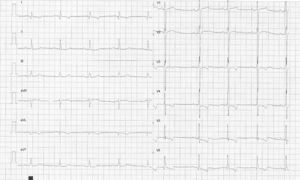

Pruebas complementariasAnalítica general: glucosa 87mg/dl, urea 45mg/dl, creatinina 1,2mg/dl, colesterol total 176mg/dl, HDL 43mg/dl, triglicéridos 158mg/dl. Hemograma 3 series normales. Rx de tórax: índice cardiotorácico normal, elongación aórtica, no datos de hipertensión venocapilar, sin otros hallazgos de interés. Electrocardiograma: ritmo sinusal a 70 latidos por minuto, eje QRS 70°, onda q en I y aVL, hipertrofia de ventrículo izquierdo según criterio de Sokolov (onda S en V2+onda R en V5 igual a 41mm). Descenso del segmento ST con pendiente descendente y T negativa asimétrica en I y aVL y de V3 a V6 (patrón de sobrecarga sistólica en derivaciones de cara lateral alta y baja) (fig. 1). Ecocardiograma: hipertrofia concéntrica moderada de ventrículo izquierdo (VI) de predominio a nivel de septo basal (septo sigmoide). Fracción de eyección de VI 67% por método de Simpson. Patrón de disfunción diastólica grado I de la clasificación de la Clínica Mayo1,2. Aurícula izquierda levemente dilatada. Válvula mitral normal. Raiz aórtica y aorta ascendente levemente dilatadas. Válvula aórtica con esclerosis leve y apertura normal. Ausencia de gradiente dinámico en tracto de salida de VI. Cavidades derechas normales. No derrame pericárdico.